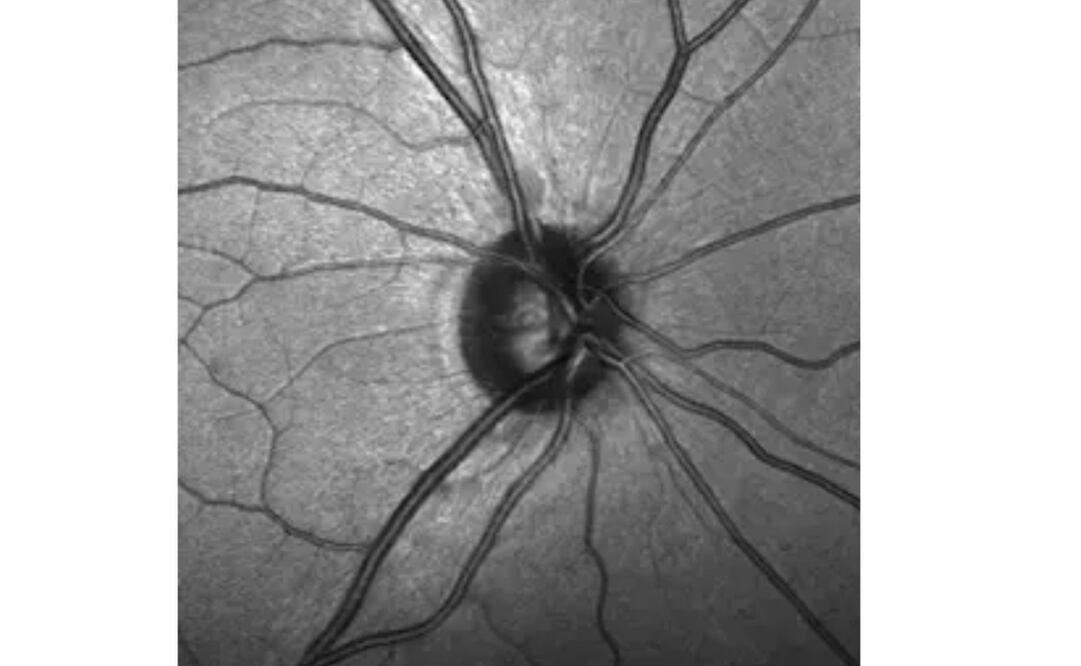

Para hacer el descubrimiento de la investigación, examinaron una estrecha banda de tejido llamada lámina del nervio óptico. Menos de 1 milímetro de ancho, la lámina se encuentra entre el tejido de la retina sensible a la luz en la parte posterior del ojo y el nervio óptico. Las largas fibras de células nerviosas se extienden desde la retina a través de la lámina, hasta el nervio óptico.

Lo que los investigadores descubrieron es que las células progenitoras de la lámina pueden ser las responsables de aislar las fibras inmediatamente después de que salen del ojo, apoyando las conexiones entre las células nerviosas en el camino hacia el cerebro.

Las células madre en el nicho de la lámina bañan estas extensiones de neuronas con factores de crecimiento, así como ayudan en la formación de la vaina aislante. Los investigadores pudieron confirmar la presencia de estas células madre utilizando anticuerpos y animales genéticamente modificados que identificaron los marcadores de proteína específicos en las células madre neuronales.